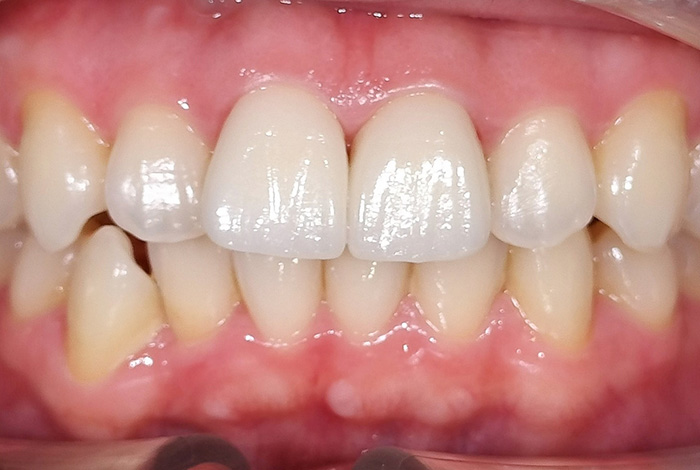

インビザラインによる全体矯正後に補綴治療を行い、咬合と審美性を総合的に改善した症例です。

まずマウスピース型矯正装置(インビザライン)により歯列および咬合関係を整え、その後、必要部位にジルコニア補綴を行いました。

矯正のみ・補綴のみではなく、両治療を組み合わせることで機能性と審美性の両立を目指した包括的治療です。